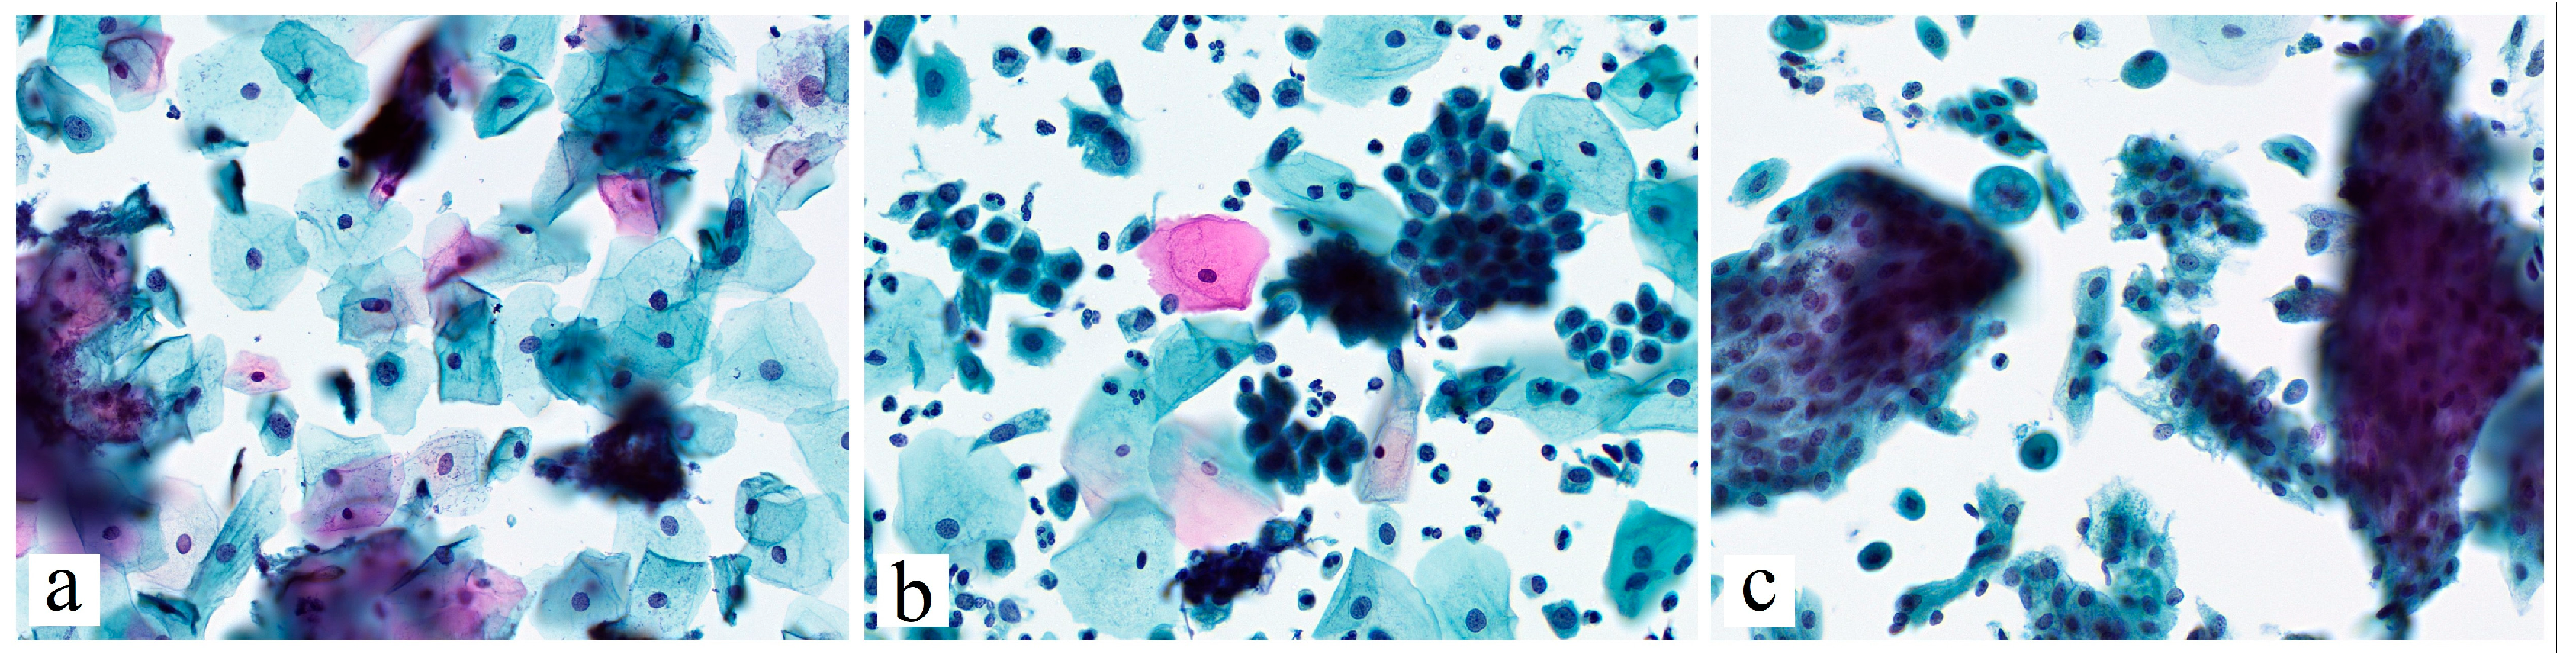

Figure 1. Main cytological categories included to the investigation (according to Bethesda system (2014)). (a)—ASC-US. The squamous cells with slightly hyperchromatic and enlarged nuclei, as well as irregular nuclear membrane contours; (b)—ASC-H. Groups of metaplastic cells with high N:C ratio, irregular nuclear membranes, enlarged and hyperchromatic nuclei; (c)—AGC. Clusters of glandular cells with nuclear enlargement, crowding and disordered arrangement. Papanicolaou stain, ×400.